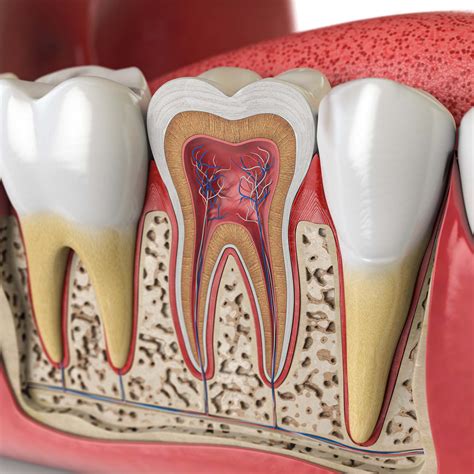

Dentist examining a tooth

A root canal treatment is a specialized procedure designed to save a tooth that has been severely damaged by decay, disease, or trauma. During the process, the infected or inflamed pulp inside the tooth is carefully removed. The inside of the tooth is then cleaned, disinfected, shaped, and filled with a rubber-like material called gutta-percha. Finally, a crown or filling is placed to seal the tooth and restore its full function.

Although the goal of this procedure is to eliminate pain, post-operative sensitivity is common as the surrounding tissues heal. However, if you are experiencing Rct teeth pain that keeps you up at night or prevents you from eating, it is vital to investigate the underlying cause rather than simply ignoring it.